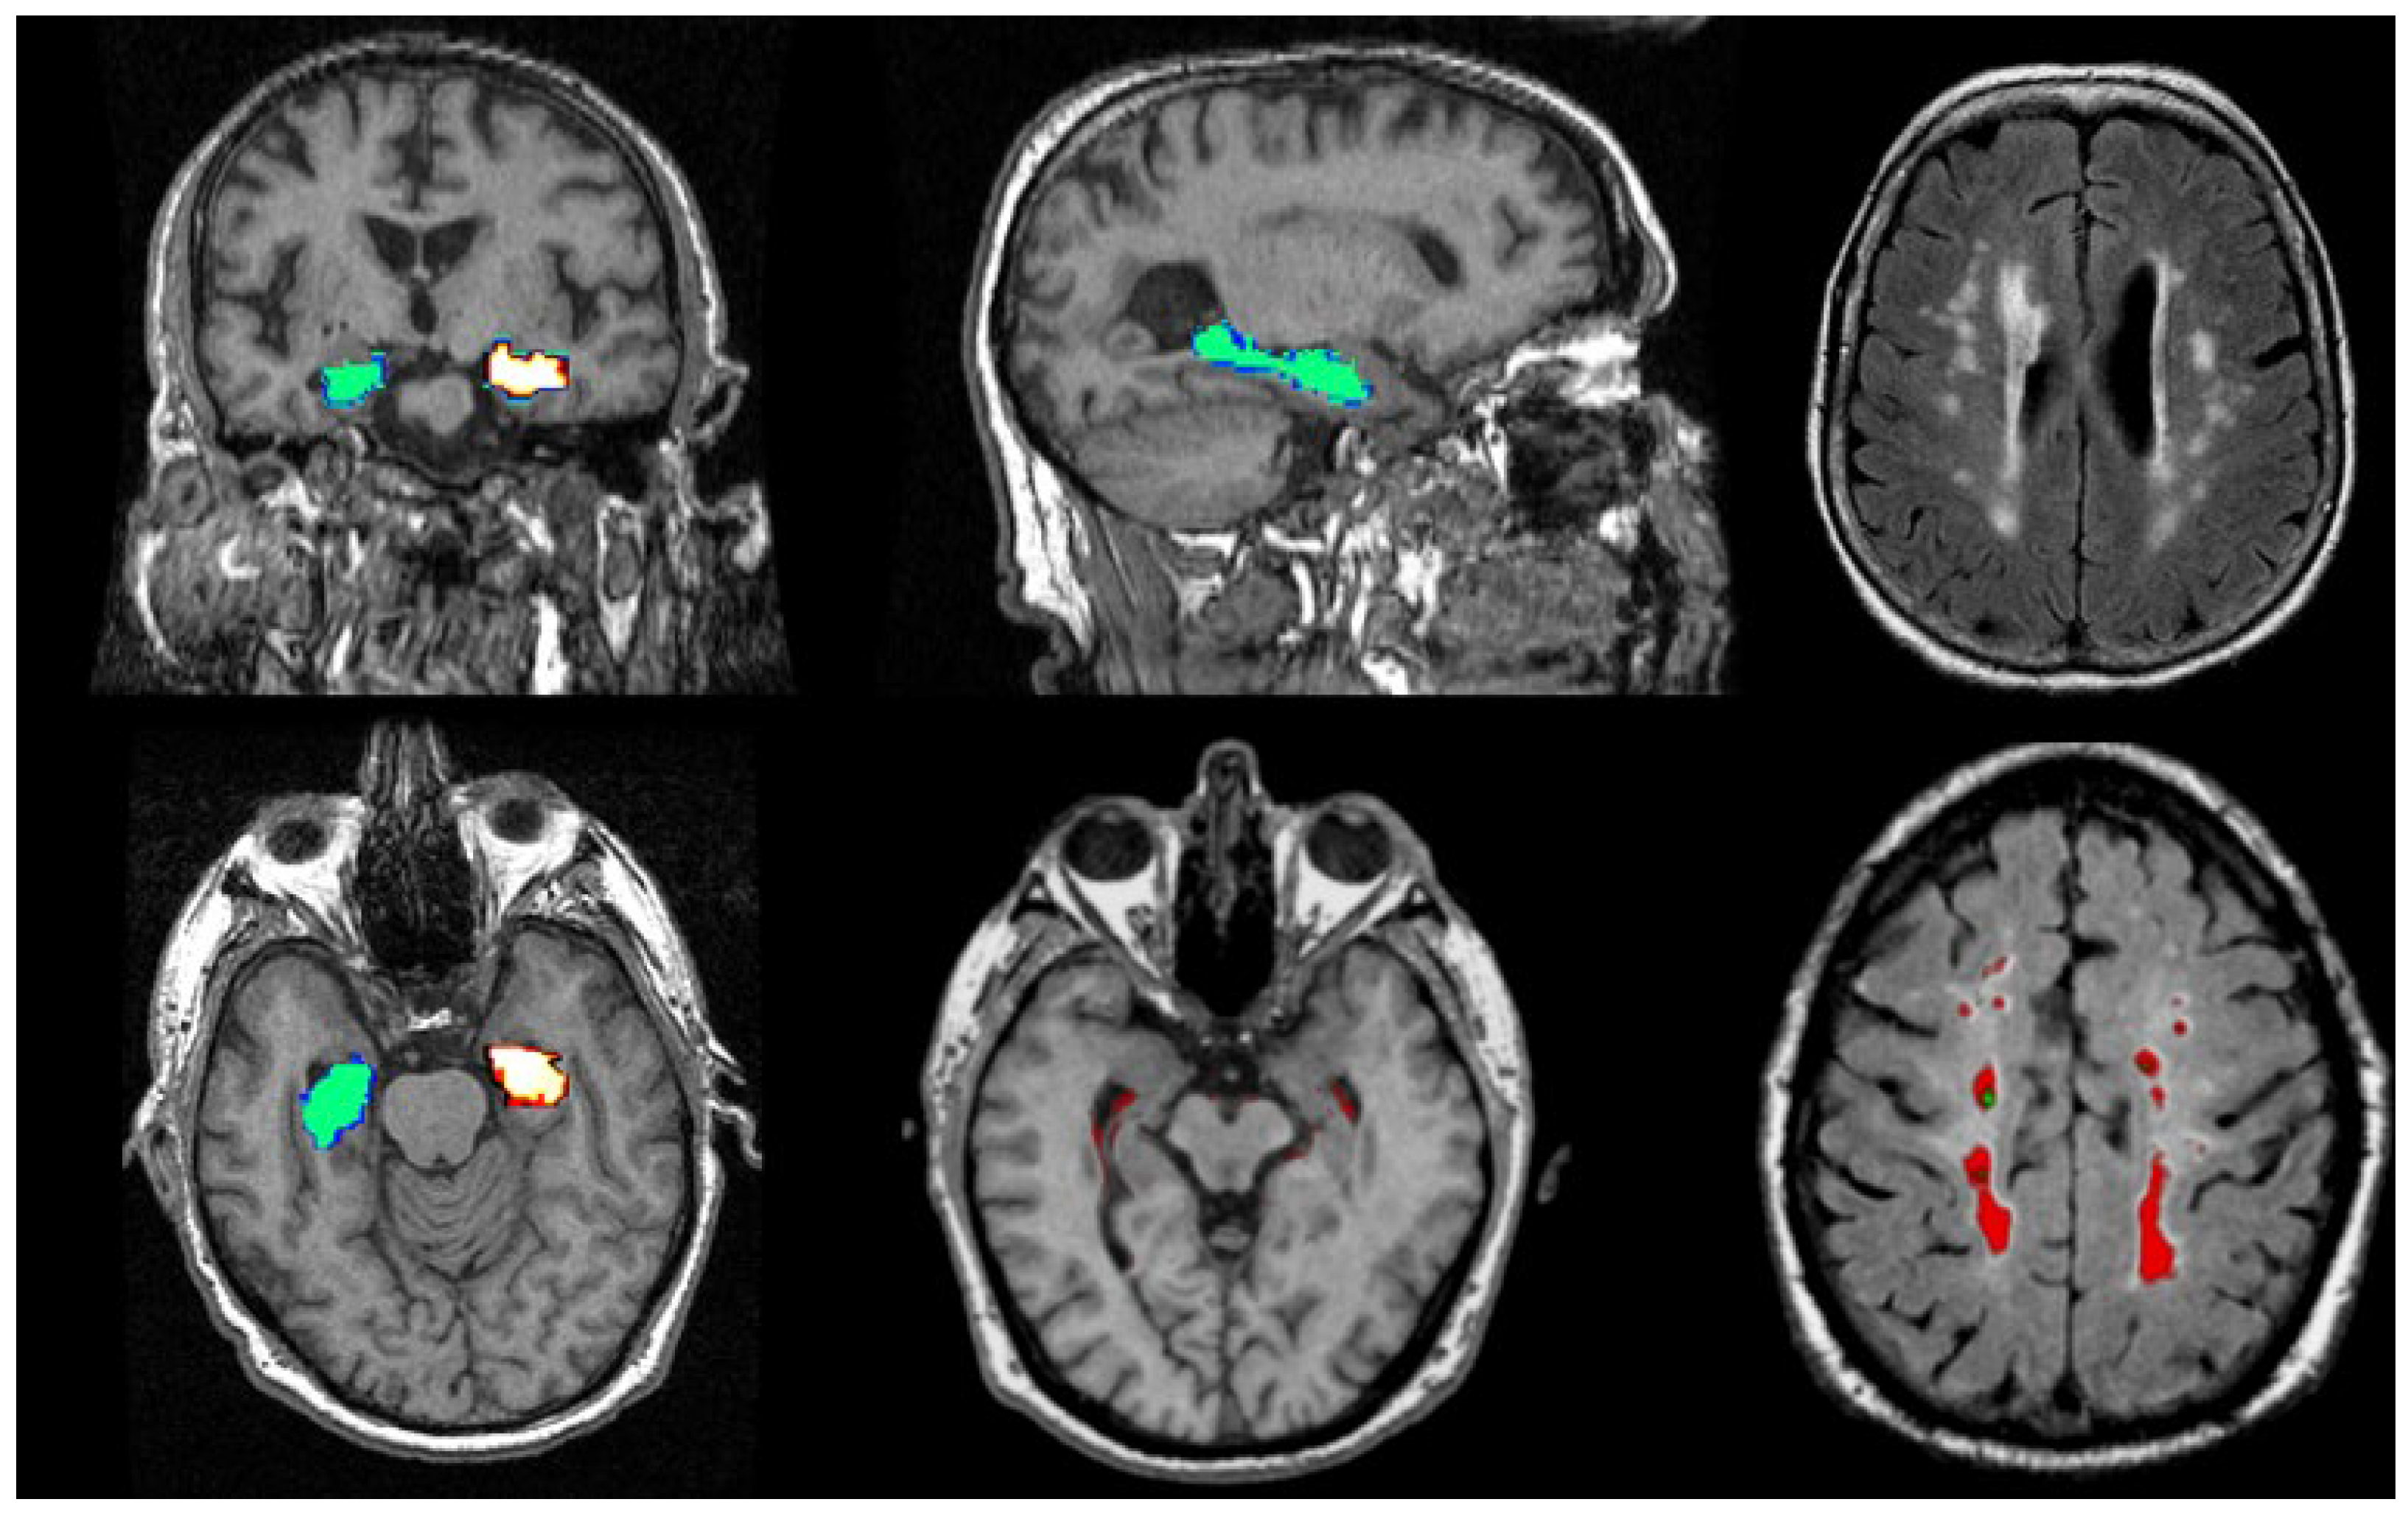

Figure 6.

Illustrations of MRI biomarkers in AD showing hippocampal volume (green and golden) in participants from the Aberdeen Birth Cohort 1936 study, illustrating hippocampal volume measurement (top row: left and centre; bottom row: left and centre), and white matter hyperintensities (top row: right, bottom row: right) in white and red. (Courtesy—Alison D. Murray, University of Aberdeen).

Figure 7.

Illustrations to show co-existing WMHs on MRI in people with AD. The WMH are seen as white areas around the ventricles (Courtesy—Jennifer Waymont, University of Aberdeen).